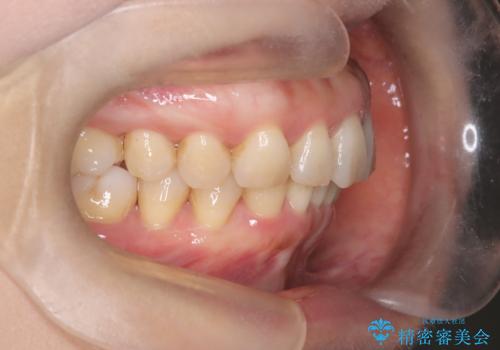

【インビザライン】出っ歯を治したい

- 前歯が出ていることを主訴に来院されました。

インビザラインにて臼歯部の遠心移動及びIPRを行なっています。

叢生量が多いケースでしたが、綺麗な歯並びとなり患者様にも満足していただきました。